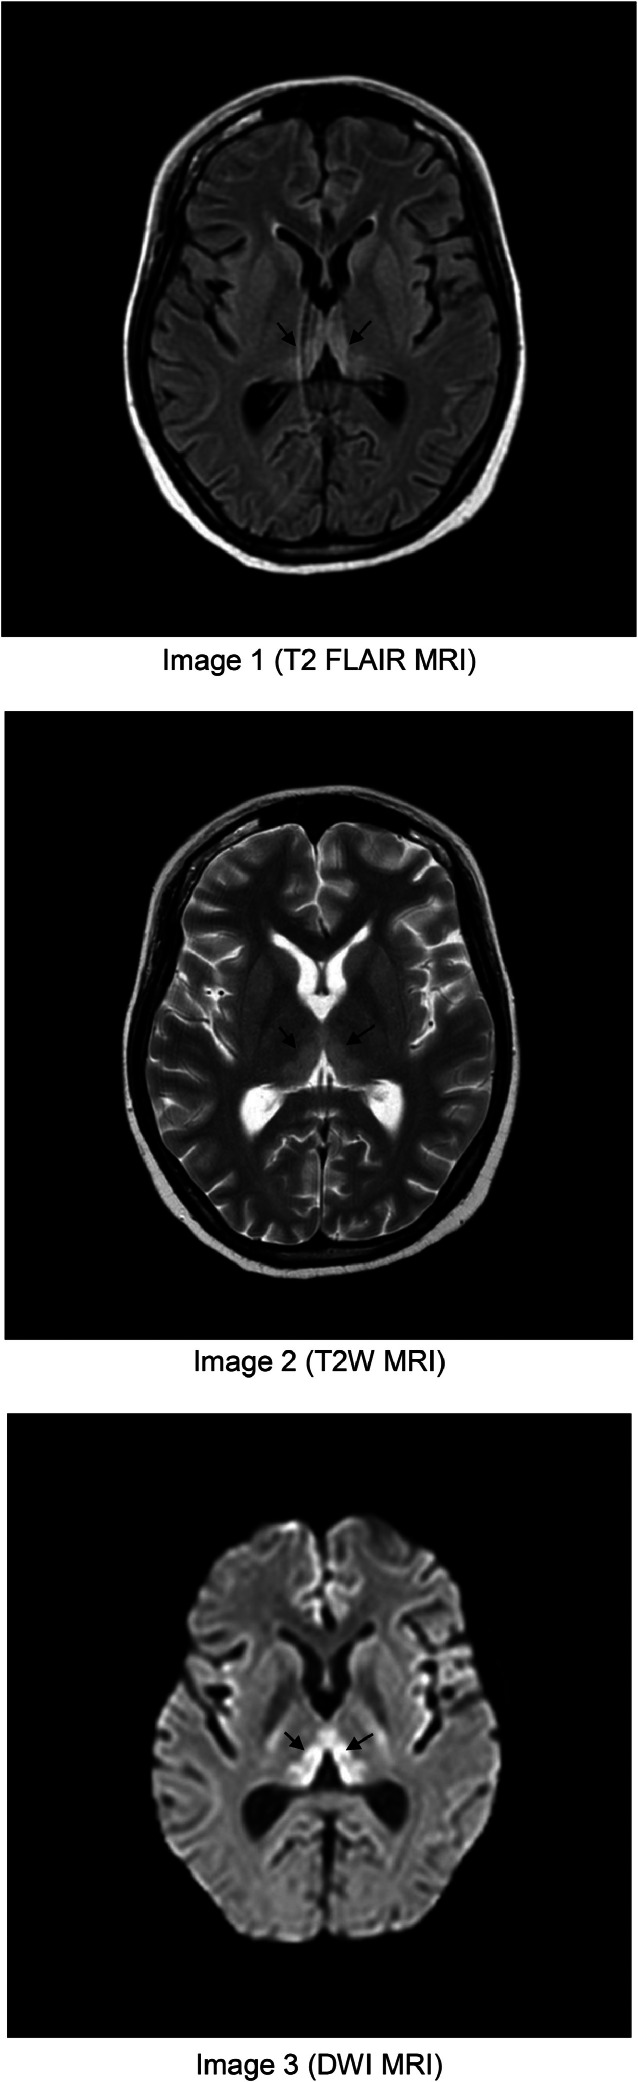

Thiamine (vitamin B1) deficiency may present with diverse symptoms and is often triggered by chronic alcoholism, severe malnutrition or hyperemesis gravidarum. While typically diagnosed clinically, atypical presentations may delay recognition and treatment. We report a 26-year-old pregnant woman in her second trimester with prolonged nausea and vomiting since early pregnancy. She developed ascending lower limb paralysis, dysarthria, horizontal nystagmus, and lagophthalmos. Initially managed as hypokalaemia periodic paralysis with thyrotoxicosis and later Guillain-Barré syndrome (GBS), her symptoms worsened despite treatment. Subsequent MRI brain imaging revealed findings indicative of Wernicke encephalopathy, prompting high-dose thiamine therapy. This resulted in significant neurological improvement. This case underscores the importance of considering thiamine deficiency in atypical neurological presentations, particularly in pregnancy. Early recognition and prompt treatment can mitigate irreversible neurological damage, emphasising the necessity of maintaining a high index of suspicion in clinical practice.